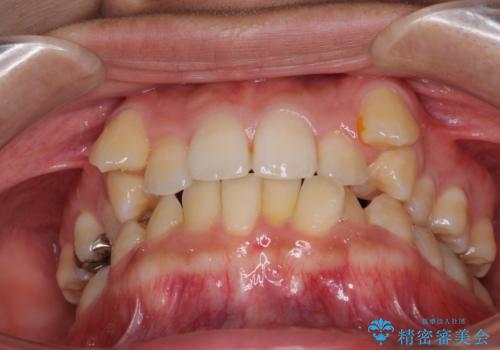

八重歯の抜歯矯正 補助装置を用いたインビザライン矯正

- 下の前歯のデコボコを気にして来院された患者様です。

来院当初、上顎の八重歯は気にしていらっしゃらなかったのですが、矯正治療をするのであれば、しっかりと治した方が良いと説明し、全顎矯正を行うこととしました。

八重歯の移動量が多く、インビザライン単体での治療は困難と判断し、補助装置により八重歯移動後にインビザラインを用いることとしました。

装着時間をしっかりと守ってくださったので、予定通りの期間で終了することができました。